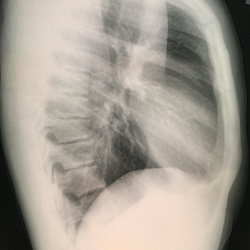

Мужчина, 42 лет, поступил с жалобами на слабость, головную боль, кашель, одышку, считает себя больным в течении 3 дней, когда появились эти жалобы, самостолятельно принимал противовоирусные...